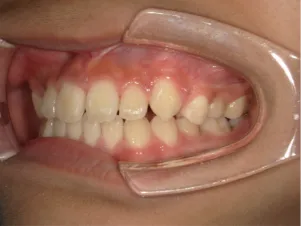

治療中④中2:マルチブラケット法へ移行:上下正中を合わせたい

*マルチブラケット法

治療後⑤中3:咬合治療終了 マルチブラケット法の期間は9か月